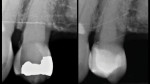

Composite offers multiple restorative modalities. The most conservative option is direct placement, which has no requirements for path of draw and insertion (Figure 1 through Figure 4). The ability to make the restorative material fit the needs of the tooth facilitates maximal conservation of tooth structure. When a tooth is severely compromised, this can be critical in restoring and extending its functionality. Alternatively, restoring with composite resin using a semi-direct technique offers the advantage of a single visit while also mitigating any polymerization shrinkage concerns associated with large composite restorations. Lastly, indirect methods using polymer blocks are also possible. When compared with ceramic materials, polymer blocks are faster to mill, place less strain on milling burs, more easily achieve fine margins, and offer favorable mechanical resistance and reparability. The ability to work with 0.5-mm minimal thicknesses can also be an advantage in occlusal wear cases.7